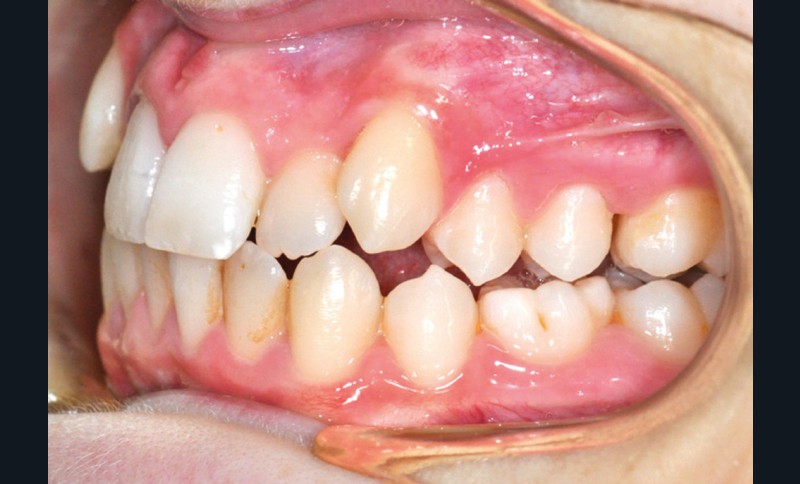

Julien nous consulte à l’âge de 11 ans et 4 mois pour des raisons essentiellement esthétiques, afin d’améliorer l’alignement de ses incisives maxillaires (fig. 1a-d) ; son chirurgien-dentiste l’a toutefois alerté sur un problème d’évolution des 35 et 47, dont l’inclusion a été mise en évidence lors d’un contrôle radiographique (fig. 1e).

L’examen intra-oral met en évidence une occlusion inversée bilatérale ainsi qu’un manque de place conséquent pour les incisives latérales maxillaires en palato-position et une infra-vestibulo-position de 13 et 23. Le patient est déjà en denture adulte jeune, hormis la persistance de la 75. L’occlusion est en classe II, plus marquée du côté droit sans engendrer de déviation des médianes incisives, d’où une mésio-position plus importante de la 13 par rapport à la 23.